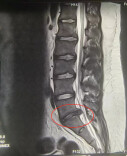

16岁的年纪60岁的腰,青少年腰椎健康问题不容忽视

2024-11-13 21:03:57 -